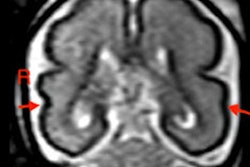

Liver imaging also isn’t expected to be affected much by the warning, said Victoria Chernyak, MD, from Columbia University in New York and the Radiology-in-Training Editor for Radiology. Current liver imaging guidelines are comprehensive and alcohol is a well-established risk factor for the development of cirrhosis and subsequent hepatocellular carcinoma (HCC).

“We know that alcohol is one of the major causes for advanced liver diseases, including cirrhosis,” she said. “Current guidelines recommend screening patients who have cirrhosis with ultrasound and AFP [alpha fetoprotein] screening every six months and in some instances, alternative imaging modalities such as CT, MRI, and abbreviated MRI.”

While Chernyak said she doesn’t immediately expect imaging protocols to change with this advisory, she added that they eventually could, if more data come out linking alcohol consumption to higher risk of HCC among patients with advanced fibrosis.